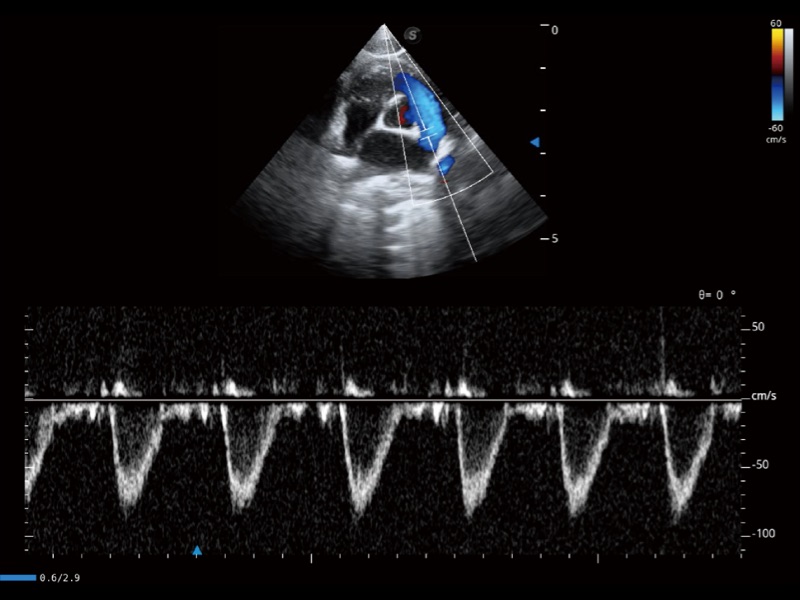

通过色彩血流和实时宽景相结合,可观察到完整的静脉或动脉的血流,方便医生检查。实时扫查过程中,如有任何操作失误也可以很容易地进行回扫擦除,而不会中断扫查。

通过360度任意调节3条M型取样线,在同一心动周期上观察心脏不同位置的运动曲线,得到准确的心功能测量数据,有效评估心肌运动及左心室功能。